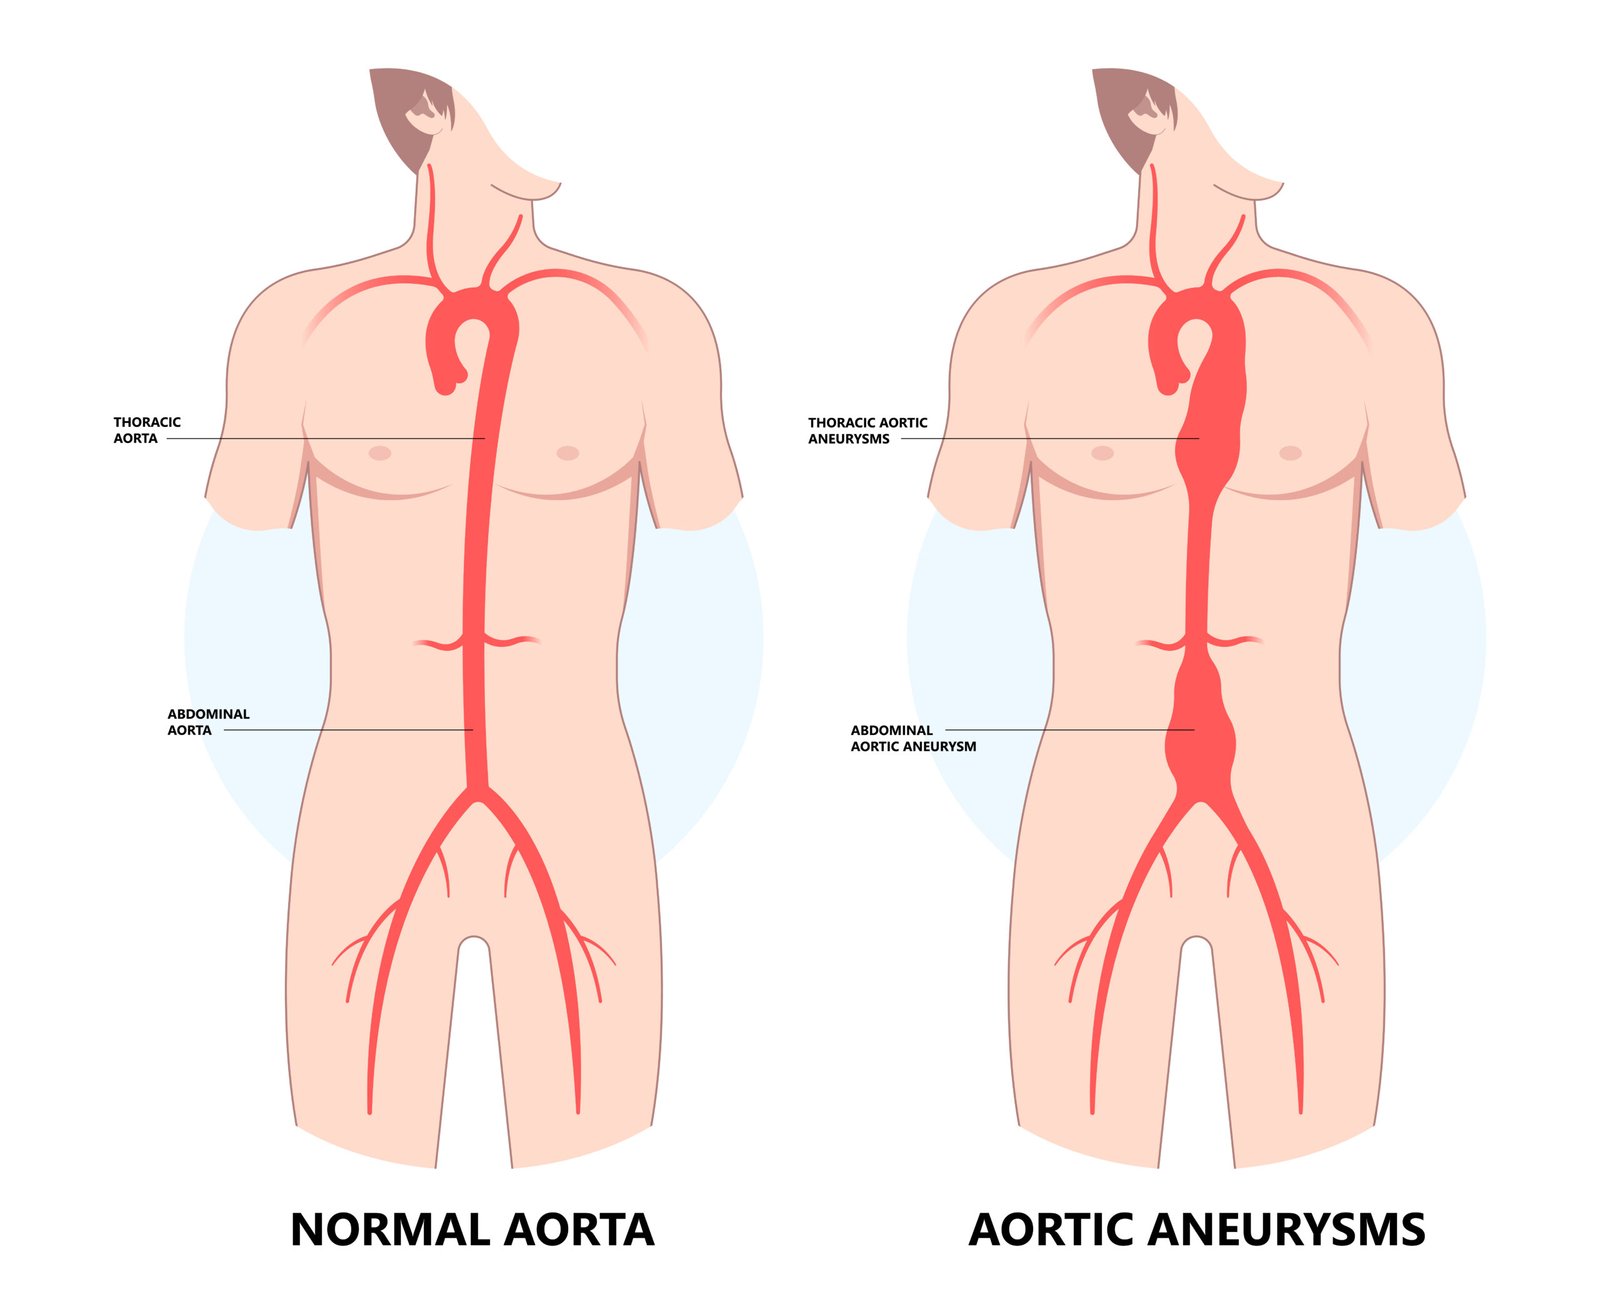

An Abdominal Aortic Aneurysm occurs when the aorta – the main artery that carries blood from your heart to the rest of your body – develops a bulge or ballooning in its abdominal section. The aorta is the largest blood vessel in the body, and an aneurysm causes it to weaken and expand.

The condition is serious because if the aneurysm grows too large, it can rupture, leading to significant internal bleeding, which can be fatal without immediate medical intervention. A ruptured AAA is one of the most common causes of death in men over the age of 65, highlighting the importance of early detection and proper treatment.